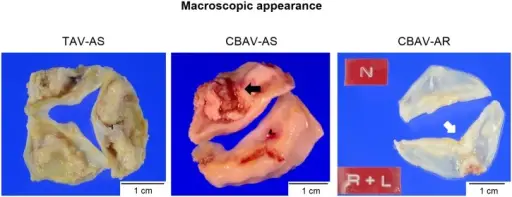

Aortic Stenosis

Aortic stenosis occurs when the aortic valve orifice narrows.

Aortic stenosis is typically brought on by fibrosis and calcification from wear and tear.

Aortic stenosis usually effects individuals above 60-years-old.

Risk factors for developing aortic stenosis include:

- Having a bicuspid aortic valve

- Rheumatic valve disease

Aortic stenosis causes a crescendo-decrescendo murmur after a systolic ejection click.

Complications of aortic stenosis include:

- Concentric left ventricular hypertrophy

- Angina

- Syncope

- Cardiac failure

- Microangiopathic hemolytic anemia

Treatment of aortic stenosis is valve replacement.